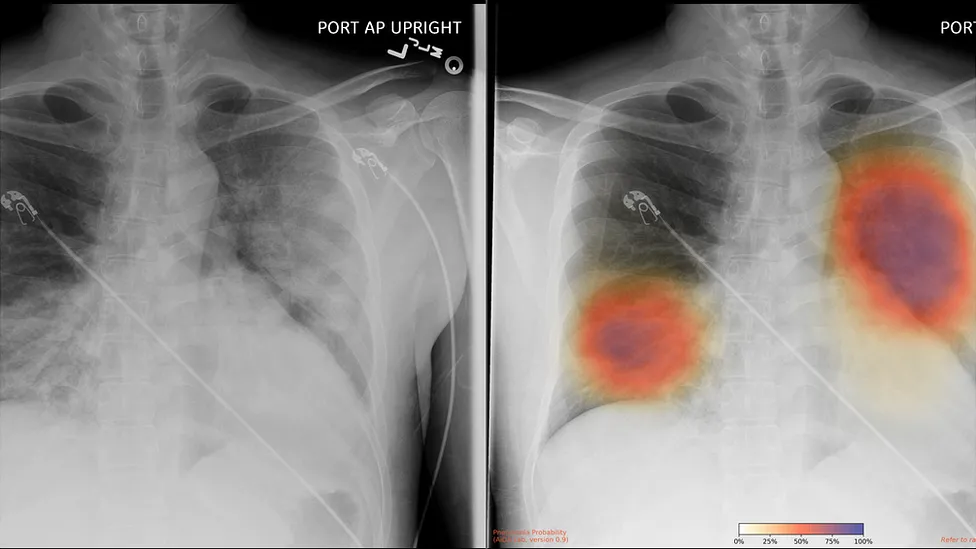

The groundbreaking way to search lungs for signs of Covid-19

When Covid-19 was at its height in China, doctors in the city of Wuhan were able to use artificial intelligence (AI) algorithms to scan the lungs of thousands of patients.

Forbes: Qure.ai Deploys AI Radiology Software In The Fight Against COVID-19

Article by Dr. James Somauroo, originally published in Forbes on how, facing a global pandemic, large healthcare organizations such as NHS have fast-tracked the adoption of innovative technologies.

MIT Tech Review: Doctors are using AI to triage covid-19 patients. The tools may be here to stay

Originally published in MIT Technology Review, this article looks at how the pandemic has accelerated AI uptake in Health care. Karen Hao the senior AI Reporter at MIT Technology Review speaks to Dr Rizwan Malik about their recent deployment of Qure AI at Royal Bolton Hospital.